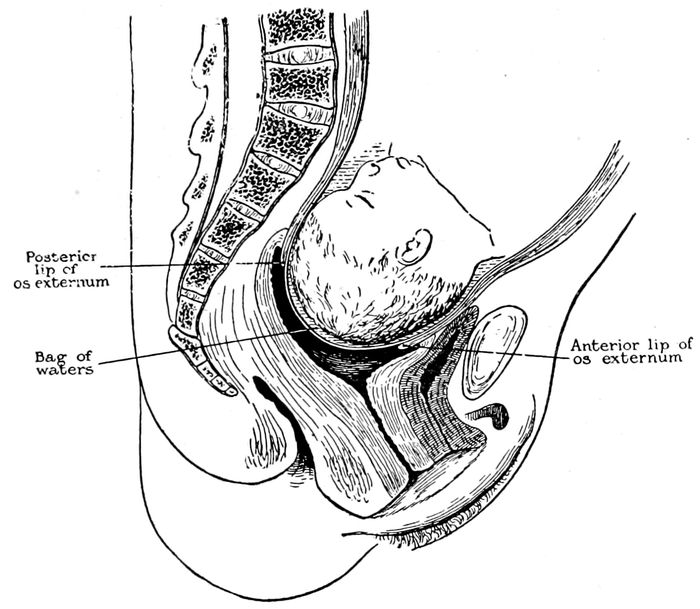

| 41. |

Child in second stage of labor |

116 |

| |